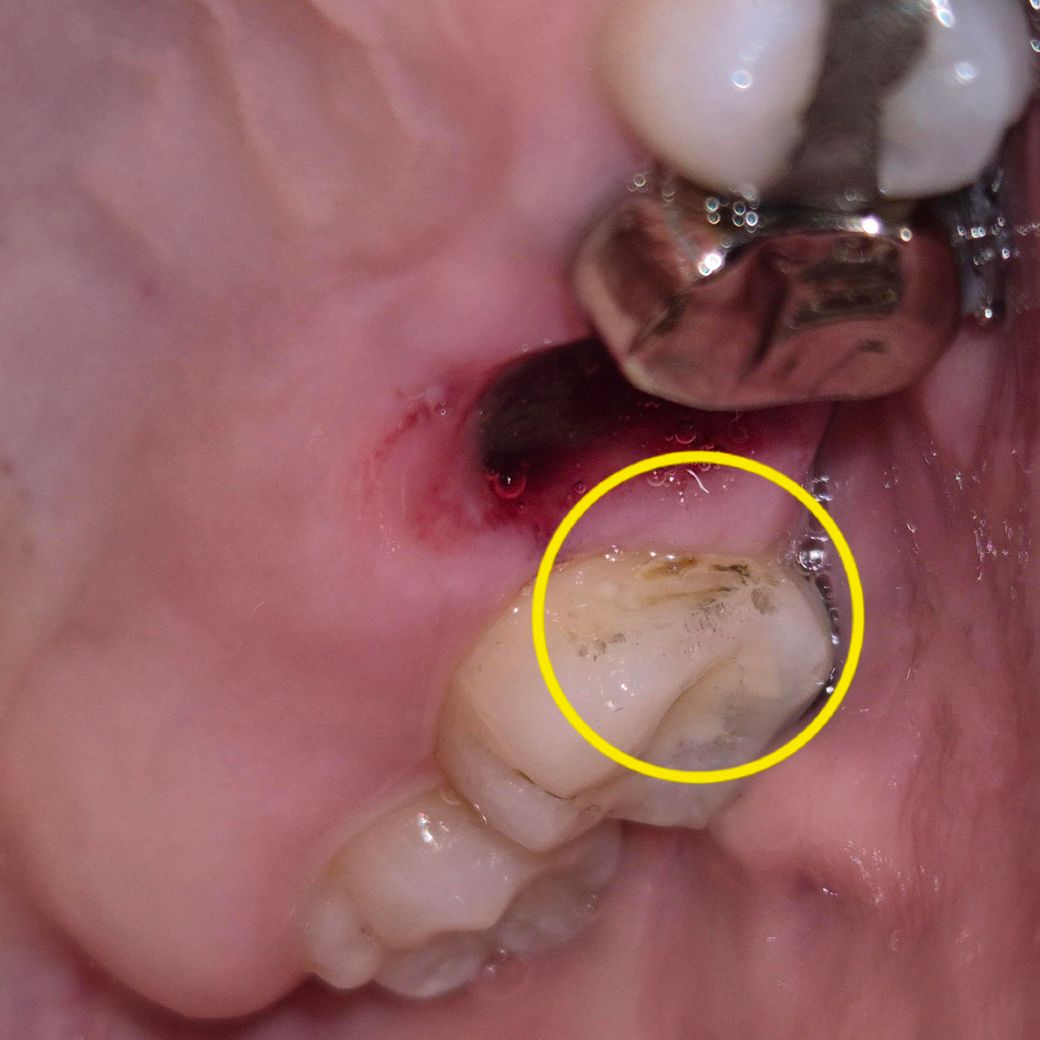

좌측 위 6번 큰어금니 발치를 했는데요, 빼고 나니까 치아 사이가 이런 자국이 있더라고요!

충치일까요..? 아니면 스케일링으로 사라질까요??

일단은 스켈링을 해봐야 되겟지만 예전에 치료한 주변으로 2차 충치가 생긴거 같긴합니다.

충치도 있고 착색도 있고 치석도 있는 것 같습니다 일단 스케일링 해보고 이어서 충치치료하세요

임상사진 만으로 정확한 평가에는 한계가 있으나, 일부 착색의 소견이 보입니다. 우식이 아닌 착색만 존재할 경우 스케일러나 표면 연마를 통해서 개선할 수 있습니다.